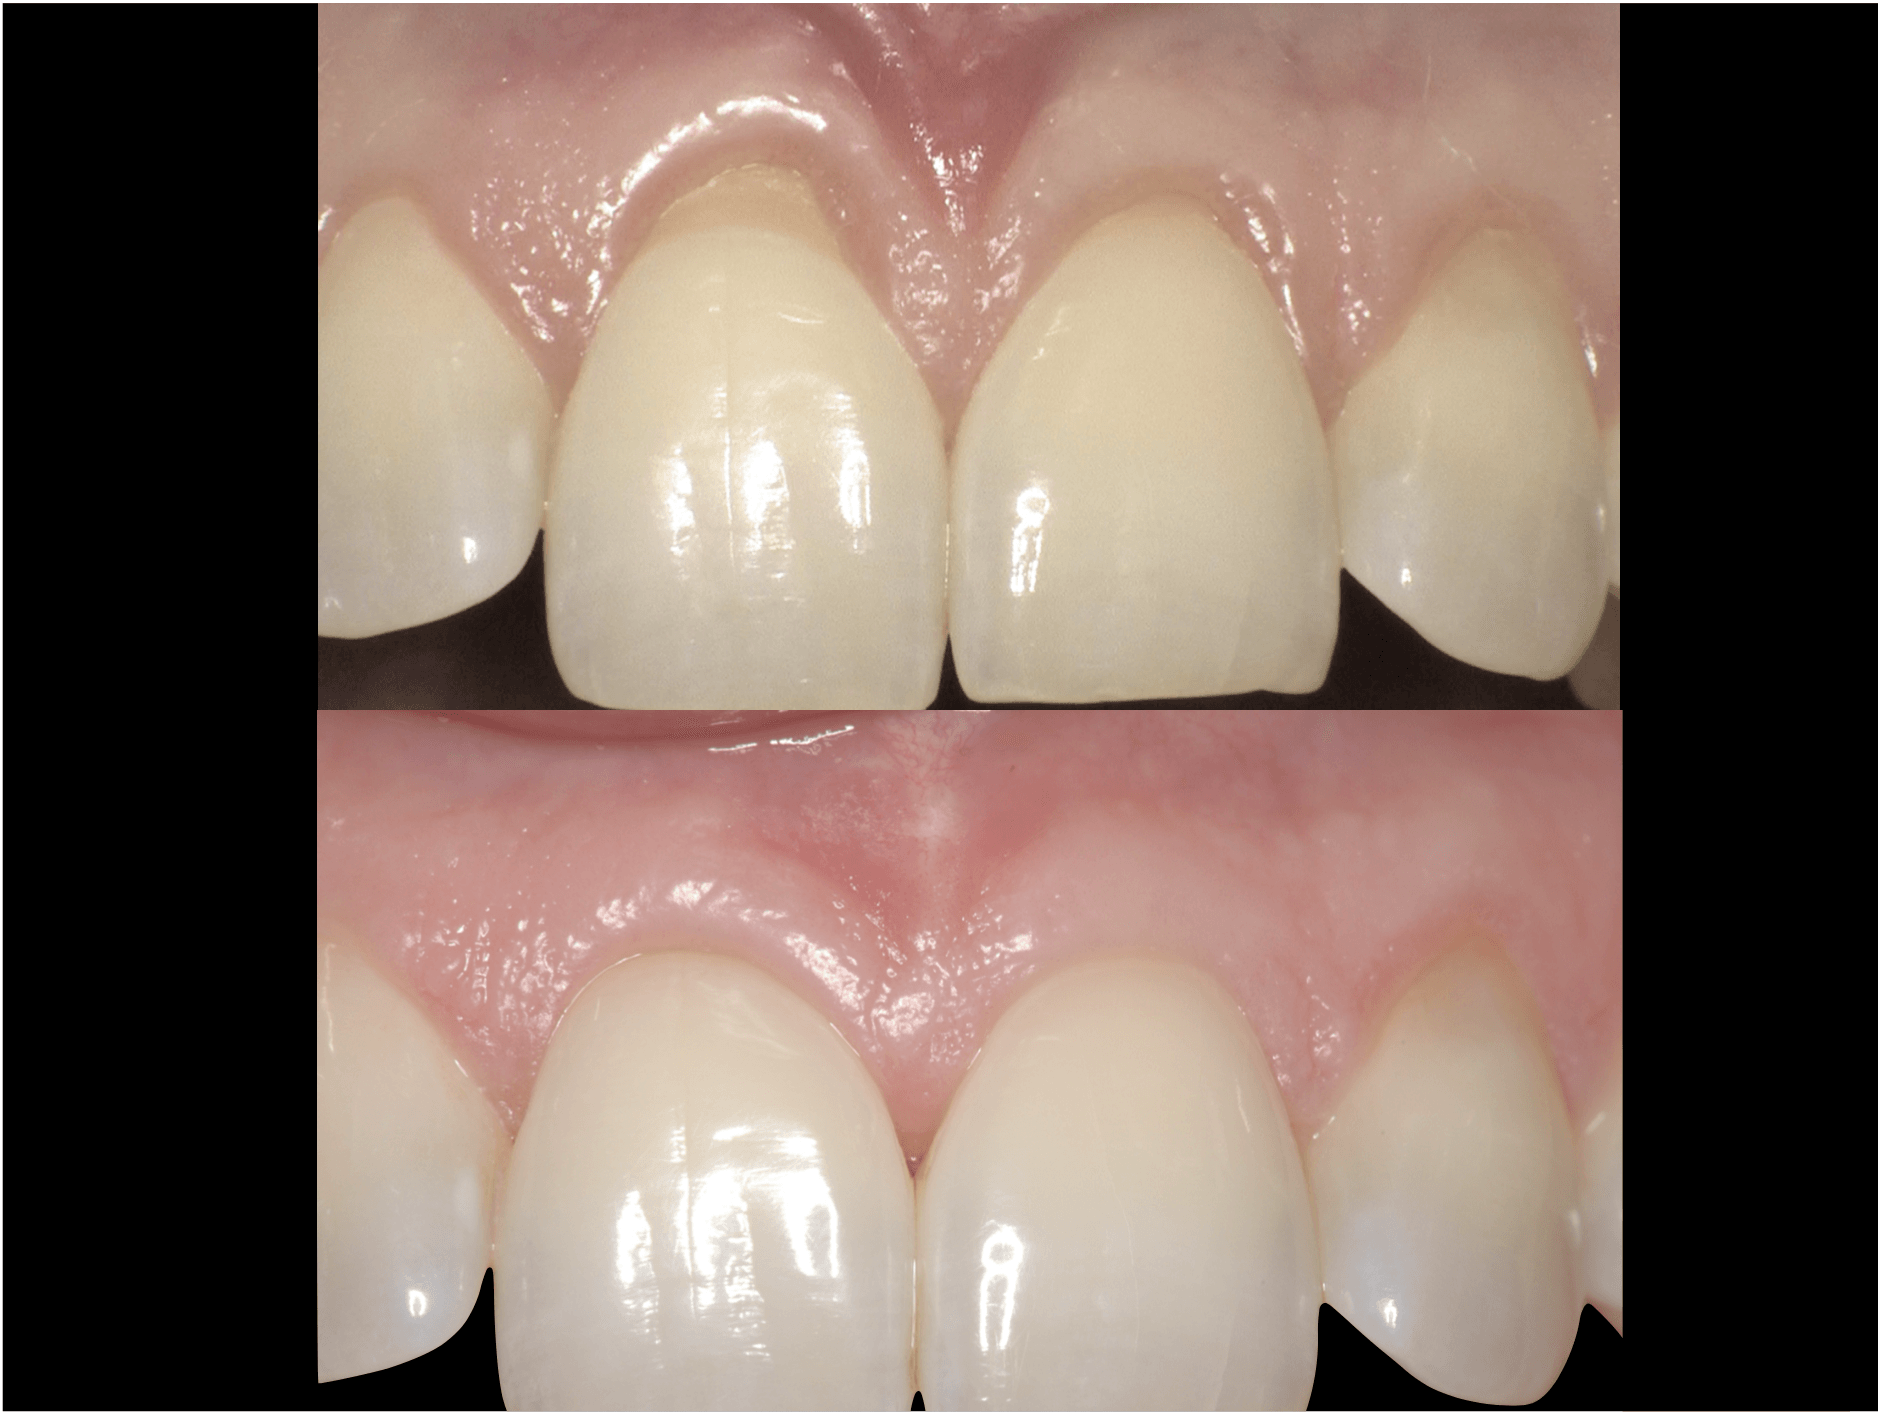

La malattia gengivale è un processo infiammatorio caratterizzato da un accentuato arrossamento, da gonfiore e sanguinamento della gengiva. La forma iniziale è la gengivite, un’infiammazione delle gengive causata da un accumulo di placca batterica. Se il paziente non osserva le manovre corrette di igiene e i controlli professionali, essa può progredire fino ad una condizione grave in cui il processo infiammatorio si estende in profondità fino all’osso di sostegno: la parodontite.

Questa patologia rappresenta una delle cause della perdita di tessuto connettivo, del riassorbimento dell’osso alveolare e della formazione di tasche parodontali che possono condurre alla perdita dei denti ed è una delle cause più comuni della perdita dei denti negli adulti. Grazie alla chirurgia orale per queste tipologie di malattie infiammatorie che colpiscono il tessuto di sostegno del dente, vengono eseguiti dei trattamenti parodontali come il curettage ( ossia il procedimento di rimozione del tartaro o della placca dalla parete orale al di sotto della gengiva) o la levigatura delle radici a cielo aperto, o ancora interventi definiti rigenerativi per l’aumento dello spessore osseo, innesti gengivali, rimozioni di cisti dentali o tumori del cavo orale. Questa tipologia d’intervento consente di ricostruire il tessuto danneggiato o perso e può avvenire in contemporanea all’intervento implantare (rigenerazione ossea perimplantare) o prima di effettuare l’intervento stesso ( rigenerazione ossea preimplantare). La rigenerazione ossea può avvenire in due modi: tramite l’auto trapianto osseo, ossia il prelievo dell’osso da una parte del corpo del paziente e l’innesto nella gengiva, oppure si procede con l’applicazione di osso artificiale, realizzato in materiale sintetico e biocompatibile, che istallato nella gengiva e ricoperto da una membrana riassorbibile, si integra perfettamente con l’osso. Il nostro studio medico dentistico, grazie alla consolidata collaborazione con il dipartimento di parodontologia della facoltà di Odontoiatria dell’Università “La Sapienza “ di Roma e alla comprovata esperienza nel campo implantologico e parodontale è in grado d’intervenire con entrambe le modalità, garantendo al paziente la massima efficienza